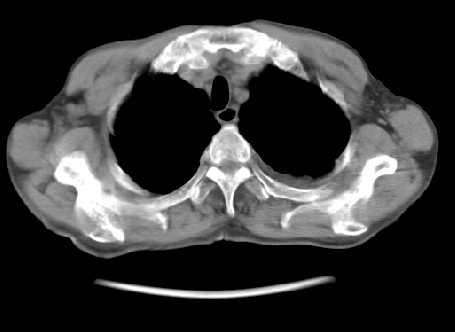

以下是引用hhcckk在2009-5-29 14:58:00的发言:[br]左上周围型肺癌,左肺门、纵隔淋巴结转移,左侧胸腔积液,左侧肋骨转移[br]

以下是引用ct诊断高手在2009-5-29 13:50:00的发言:[br]考虑左侧中央型肺癌,阻塞性肺炎伴肺不张。纵隔淋巴结转移。慢支 肺间质纤维化肺气肿。左侧胸腔积液。左侧肋骨转移?